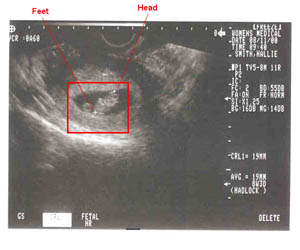

Ultrasound pictures of baby

08/11/2000--Internal ultrasound picture at 8 weeks.